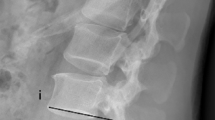

Traditional methods to improve the stability of pedicle screw are as follows: (1) Increasing the length and diameter of the screws2; (2) Improving the screw design, such as expansion screw3,4; and (3) Using bone granules or bone cement such as polymethylmethacrylate (PMMA) to strengthen the screw tunnel5,6,7. Due to the poor bone quality in osteoporosis spine, most of the methods are not effective. Although PMMA augmentation is considered a reliable and feasible method up to the present time. However, screw tunnel augmentation with PMMA is a complicated procedure, which may also increase the operation time, the amount of bleeding and the risk of PMMA leakage (approximately 30%)8. Surgeons showed great anxiety about internal fixation failure especially in the treatment of lumbar spondylolisthesis with osteoporosis. Figure 1 shows a typical case of postoperative screw loosening in this condition. To overcome this problem, authors improved the design and created a new type of hollow cement-augmented pedicle screw (CAPS) named bone cement-injectable cannulated pedicle screw (CICPS).

(A,B) A 74-year-old male diagnosed as spondylolysis at the L4 vertebral body with osteoporosis(T = −3.2, degree I). (C,D) Immediate postoperative radiographs showed reconstruction for spondylolisthesis compared with that before surgery. (E) Internal fixation failure occurred 1 month after surgery. Lateral radiograph showed L4 vertebral body was displaced again and the red arrow showed screw loosening and pullout. Patient redeveloped the lumbocrural pain. (F,G) After treatment with screw tunnel augmentation using PMMA (left side of L4 and L5, as the red arrows showed), L4 vertebral body was reset again. (H) One month after the revision surgery, however, screw failure occurred again (the red arrows showed the PMMA augmentation screw loosening).